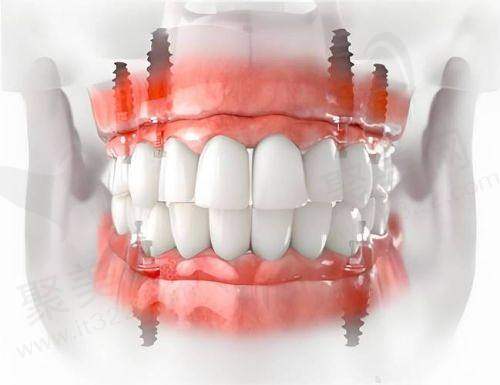

1. 连缺多颗牙:如果是连缺 6 颗牙这种情况,种植牙比镶烤瓷牙要好些。做种植牙只需植入 3 - 4 颗种植体加上连桥冠,就可以完成修复,而且咀嚼力度、咬合力量都比较好。而镶烤瓷牙需要选择至少两个健康的基牙搭桥,当缺失牙齿数量较多时,可能会面临基牙不够或者基牙不健康的问题,修复成效不理想。

后牙区咀嚼压力大,种植牙的长久稳定性更具优势。后牙主要负责咀嚼食物,需要承受较大的力量,种植牙的人工牙根能提供足够的支撑,确保牙齿在长期使用过程中不会出现问题。而烤瓷牙由于依靠邻牙承重,在长期的咀嚼压力下,基牙可能会受到损伤。

诊疗项目:种植牙,单颗种植,多颗种植,半口种植,全口种植,韩国登腾Dentium种植体,韩国奥齿泰Osstem种植体,瑞典诺贝尔Nobel种植体,瑞士ITI种植体,韩国安美齿IBS种植体,美国3I种植体,德国ICX种植体,美国皓圣Hiossen种植体,韩国DIO种植体,华西cdic种植体,美国百康Bicon种植体,德国xive种植体,德国Camlog种植体,瑞典astra种植体,韩国登特斯Dentis种植体,韩国美格真MegaGen种植体,德国贝格Bego种植体,德国费亚丹Ankylos种植体,瑞士士卓曼Straumann种植体,意大利西泰克C-Tech种植体,韩国仕诺康Snuc种植体,美国杰美Zimmer种植体,国产莱顿BLB种植体,国产威高WEGO种植体,以色列丹特因Dentin种植体,以色列柯特斯CORTEX种植体,穿颧种植,all-on-4种植牙,穿翼板种植牙技术,即刻种植牙,瑞士百丹特种植体,法国安卓健Anthogyr种植体,上颌窦提升术,韩国纽百特NeoBiotech种植体,all-on-6种植牙